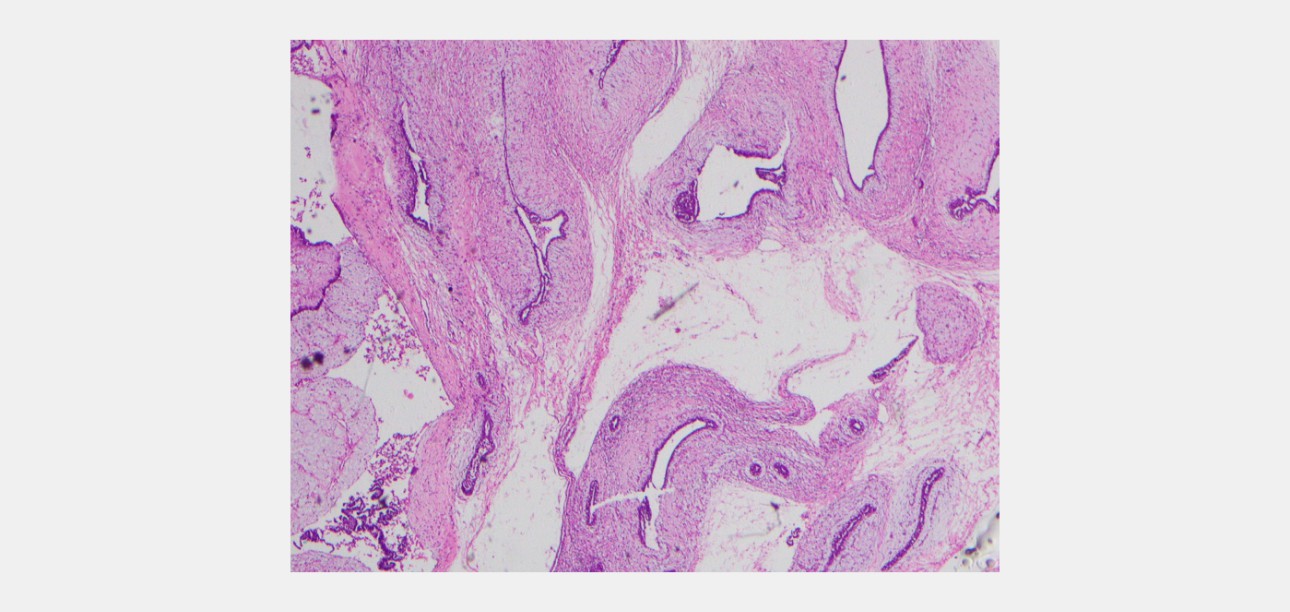

Histology Findings

6 core biopsies were taken. Sections reveal fibroadenoma composed of slit-like compressed glandular structures lined by a dual population of cells; surrounded by a myxoid stroma. There is no nuclear atypia or mitotic activity in the stroma. No evidence of DCIS or malignancy.

swe-prior-breast-mass-fig4-pc

Figure 4- Core biopsy specimen of the breast from patient B